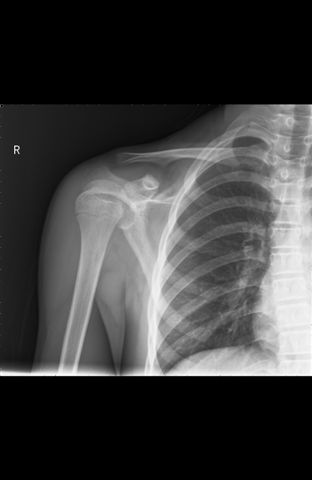

高处跌落,48天前曾被诊断右肱骨外科颈骨折,

48天前第一次拍片:

第一片及一月前复查片肱骨外科颈下内缘均象有骨折,因为每次肱骨体位不同所显示不同,应维持考虑骨折诊断,建议复查或作ct或mri检查。

这么年轻,果是骨折48天也应该有骨痂生成吧,而不是像现在:样低密度影这样光滑

第一张片感觉外科不顺,提示外科颈骨折可能。随访

第一次诊断为骨折是正确的,看左侧对比,右肱骨上段内侧的骨质有轻微凹陷。